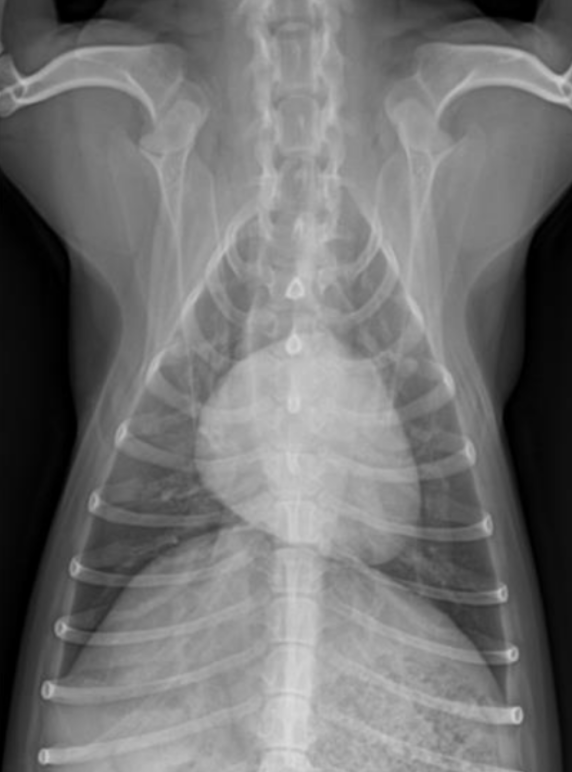

| DV (Dorso-ventral) | VD (Ventro-dorsal) |

|---|---|

![]() | ![]() |

| 심장 관찰에 좋음. | 폐 관찰에 좋음. |

| 기흉 있을 때 좋음. (pleural air) | 흉수 있을 때 좋음. (pleural fluid) (바르게 놓인 삼각형 모양 - 흉수가 아래-옆으로 퍼짐) |

| 응급 환자에서 필요. (원래 자세 그대로) |